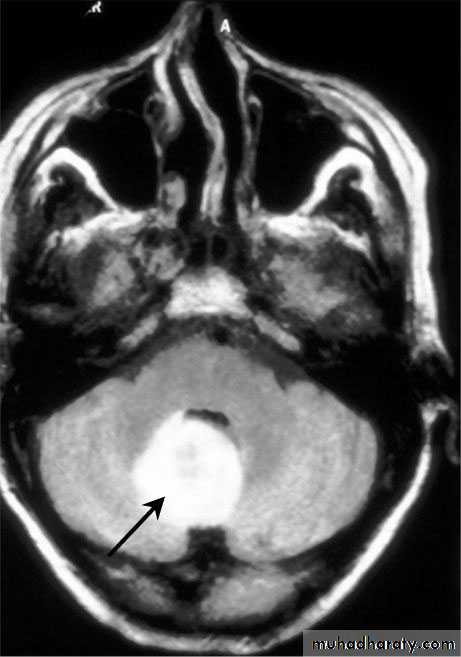

Cerebellar Abscess